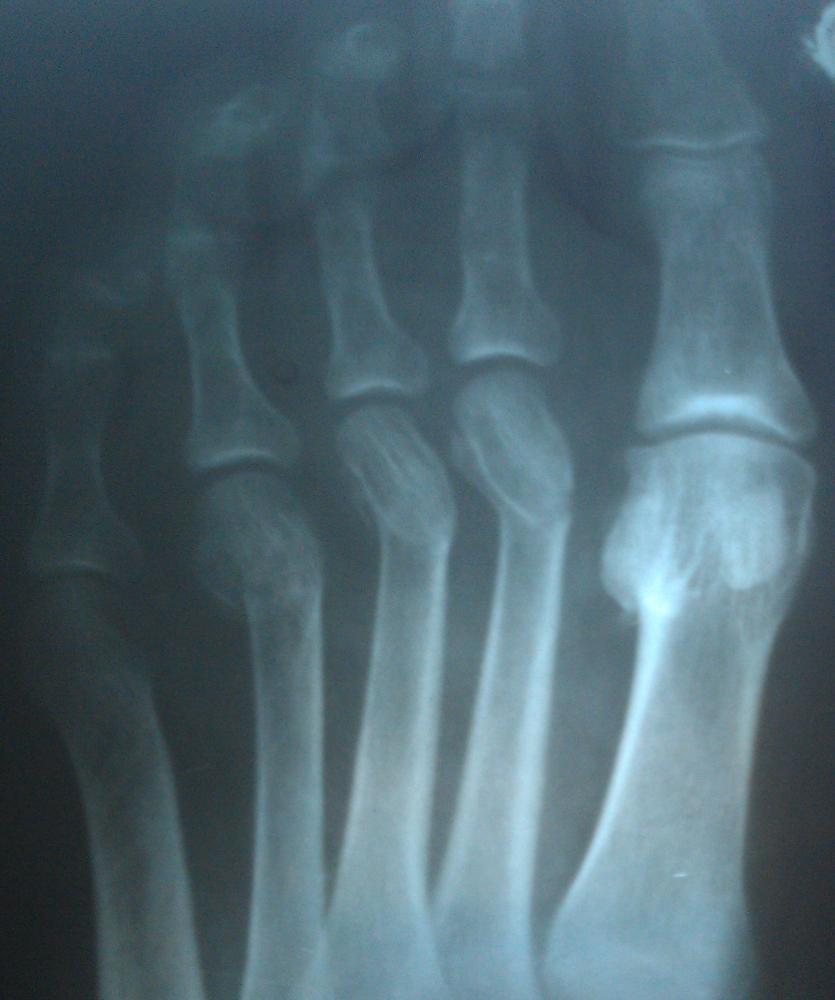

Перелом пальца ноги? Рентгеновский снимок.

В общем есть рентгеновский снимок пальцев ноги.

Где делали рентген, сказали - сломаны 2,3,4 палец.

Травматолог посмотрел снимок - сказал, ушиб, переломы очень старые.

Кому верить? Гипс не поставили, просто дома в покое быть назначили (не мне).

Я так посмотрел другие рентгеновские снимки переломов пальцев ног в интернете - вроде нет переломов никаких.

Костную мозоль вижу. Ткани вокруг воспалены и очаг воспаления четко локализован. Конкретно травмы на снимке не видно. Мбыть старая трещина надумала подпортить жизнь? Дальше коновальствовать не рискну.